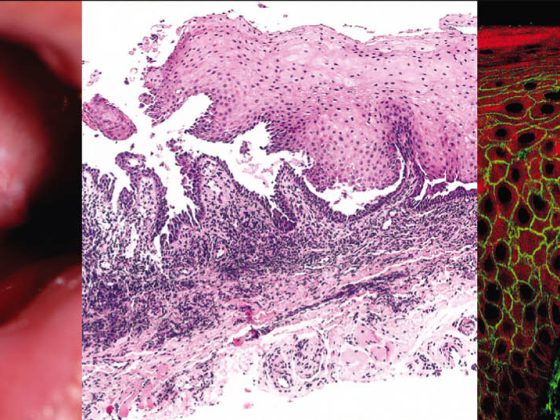

Die Vaskulitiden sind eine sehr heterogene Gruppe von Erkrankungen, welche in allen Altersgruppen auftreten können. Im Prinzip handelt es sich um Entzündungsvorgänge in den Gefässwänden mit nachfolgender Gewebeschädigung. Die klinische Bandbreite ist gross und reicht von der wenig symptomatischen, selbstlimitierenden und auf die Haut beschränkten Vaskulitis bis hin zur lebensbedrohlichen Systemvaskulitis.